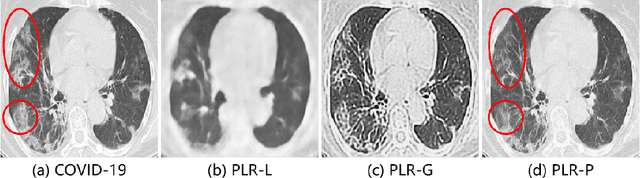

Abstract:The Coronavirus disease 2019 (COVID-19) has rapidly spread all over the world since its first report in December 2019 and thoracic computed tomography (CT) has become one of the main tools for its diagnosis. In recent years, deep learning-based approaches have shown impressive performance in myriad image recognition tasks. However, they usually require a large number of annotated data for training. Inspired by Ground Glass Opacity (GGO), a common finding in COIVD-19 patient's CT scans, we proposed in this paper a novel self-supervised pretraining method based on pseudo lesions generation and restoration for COVID-19 diagnosis. We used Perlin noise, a gradient noise based mathematical model, to generate lesion-like patterns, which were then randomly pasted to the lung regions of normal CT images to generate pseudo COVID-19 images. The pairs of normal and pseudo COVID-19 images were then used to train an encoder-decoder architecture based U-Net for image restoration, which does not require any labelled data. The pretrained encoder was then fine-tuned using labelled data for COVID-19 diagnosis task. Two public COVID-19 diagnosis datasets made up of CT images were employed for evaluation. Comprehensive experimental results demonstrated that the proposed self-supervised learning approach could extract better feature representation for COVID-19 diagnosis and the accuracy of the proposed method outperformed the supervised model pretrained on large scale images by 6.57% and 3.03% on SARS-CoV-2 dataset and Jinan COVID-19 dataset, respectively.